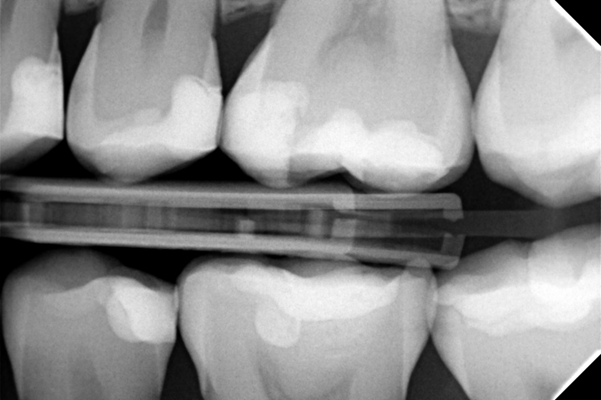

La paciente acudió a la clínica para un chequeo anual. Tras un examen clínico y radiográfico, se diagnosticó una lesión de caries secundaria en la superficie oclusal del diente 26, así como dos lesiones cariosas adicionales en las superficies distales de los dientes 24 y 25. La paciente no refirió síntomas específicos. El tratamiento indicado consiste en la colocación de una restauración Clase I en el diente 26 y restauraciones Clase II en los dientes 24 y 25.

Como puede observarse en las imágenes finales, la resina Transcend™ ofrece una apariencia estética excepcional para la restauración. El sistema de matrices seccionales Halo permitió lograr una excelente anatomía proximal, tal como se aprecia en la radiografía.